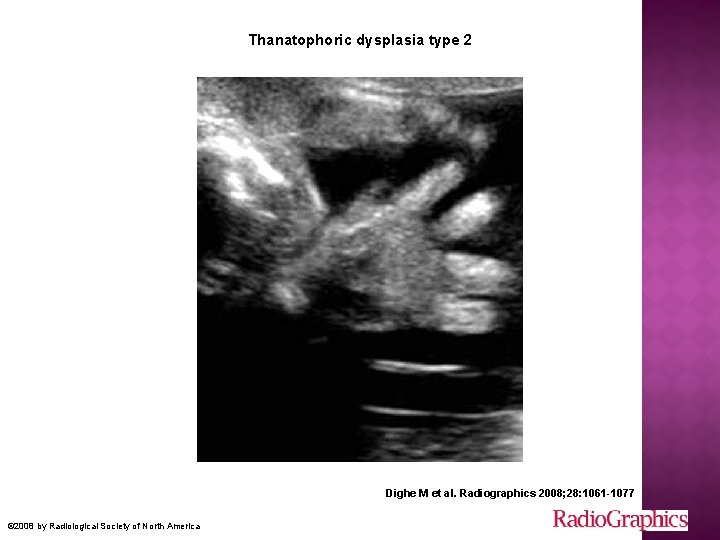

� Tanatrofik « ölümcül » � En sık letal fetal iskelet displazisi � Fibroblast growth factor receptor 3 (FGFR 3) gen mutasyonu � OD (genellikle) � 2 tipi var Genellikle erken yenidoğan döneminde pulmoner hipoplazi nedeniyle kaybedilir

Ciddi ekstremite kısalığı Tip 1’ de eğimli Tip 2’ de düz � Tip 1 makrosefali frontal bossing burun kökü basık � Tip 2 cloverleaf trident hand torakal hipoplazi telephone receiver Ekstremitelerde ileri derecede açılanma ve kısalık Uzun kemikler düz ve kısa

Thanatophoric dysplasia type 2 Dighe M et al. Radiographics 2008; 28: 1061 -1077 © 2008 by Radiological Society of North America

Thanatophoric dysplasia type 2. Dighe M et al. Radiographics 2008; 28: 1061 -1077 © 2008 by Radiological Society of North America